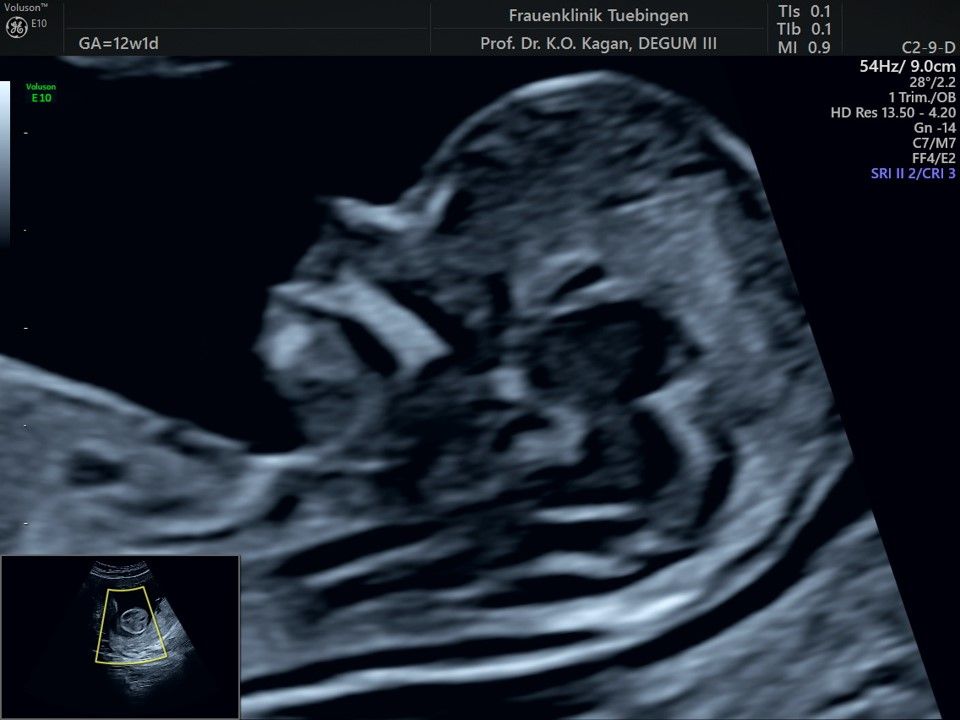

Im Rahmen des Ersttrimester-Screenings untersuchen wir die Organe des Feten mittels Ultraschall. Dabei machen wir auch gerne ein Bild für Sie.

Obwohl der Fet zu diesem Zeitpunkt erst zwischen 5 und 8cm groß ist, lassen sich bereits etwa die Hälfte aller schwerwiegenden Fehlbildungen erkennen bzw. ausschließen. Sollten wir eine Auffälligkeit sehen, werden wir mit Ihnen den Befund und das weitere Vorgehen ausführlich besprechen.

Die eigentliche Organuntersuchung findet um die 20.SSW (zweites Screening) statt. Das Ersttrimester-Screening und das zweite Screening sind sich ergänzende Untersuchungen und ersetzen sich gegenseitig nicht.

Bauchwanddefekt